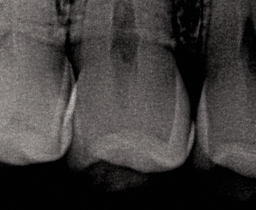

A topical anesthetic was placed on the papila. A fender wedge was placed preoperatively to protect the adjacent tooth (Fig. 2).

Fig. 2 Fig. 3

The contact was broken bucco-lingually and gingivally with the fender wedge in place (Fig. 3). The fender wedge was removed in order to evaluate the prep (Fig. 4).